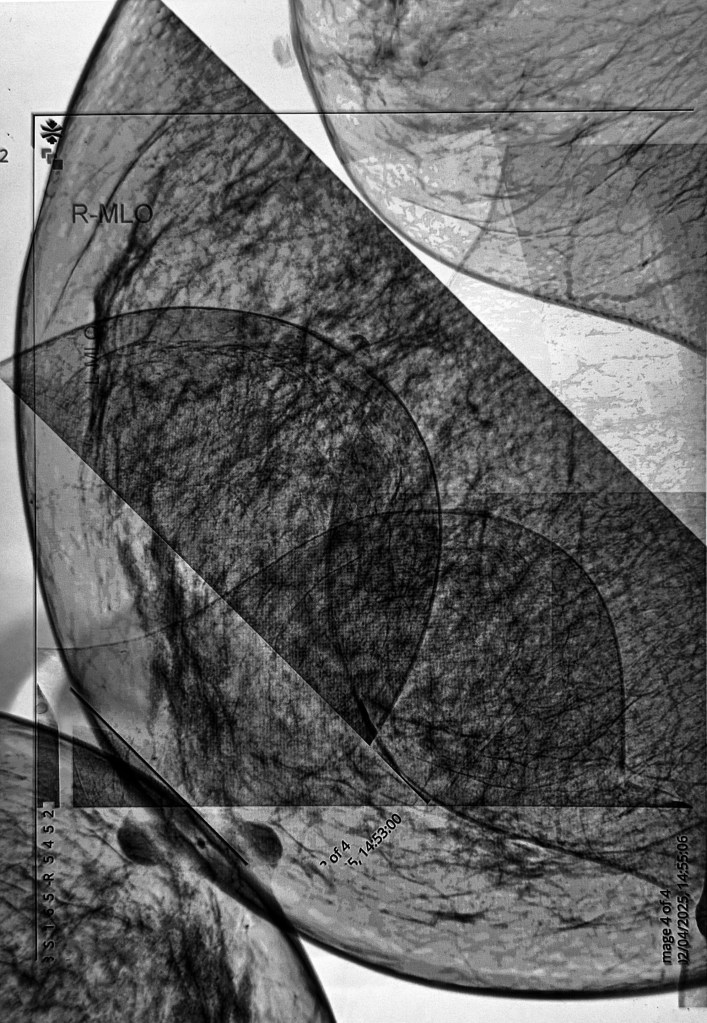

I took all four images: right and left mediolateral oblique and right and left craniocaudal. I removed my personal info and removed some digits from my hospital number as I wanted it to be apparent that they are medical images. I then imported them into Procreate and played around with inverting and layering etc. And this is when I learnt an important lesson – whilst it’s great to experiment and try lots of different things, if you don’t make a note of it somewhere you won’t be able to recreate it. I liked the first image I made but wanted to adjust some of the transparency in some areas. So I adjusted it but couldn’t remember what I had done to create the final image. Try as I might I just couldn’t recreate it so, in the end, I decided to run with the original image. I displayed the image on my laptop screen and then took a photograph of it which incorporated some of the reflections on the screen, which I think add a bit of depth and additional interest to the image. The idea was to print it and then overdraw with pencils, charcoal etc. I experimented on a home-printed image. I became even more despondent because nothing seemed to work. I decided to fold it, scrunch it and cut it up. Then I thought, a good approach when something isn’t working is to cut it into strips and weave it. I liked the effect, and my mood lifted.

Anyway, when I got the A3 image from the printers I didn’t think it was that bad, and I couldn’t bring myself to cut it up so I just overdrew some areas adjusting tones using black, grey and silver pencils and some charcoal. I quite like how the inclusion of the straight lines and the curves suggest a graph of some sort, how it has both a geometric feel but also a natural, landscape feel, as if the line towards the centre is the waterline and beyond is a land mass, the dark area on the left almost reading as a tree. It was rolled up, so I’m going to have to flatten it and sort out proper lighting before I take a photo for submission. I actually really like it.